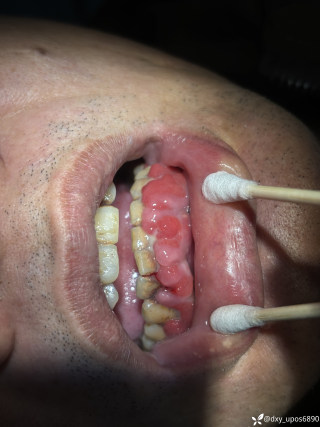

烧伤整形邹普功烧伤科医师

活动背景和目的:我从去年九月份陆续在丁香园写了几十帖有关腋臭微创手术的帖子,受到很多同行老师的关注及跟帖,其中有很多同行老师也在尝试用我的这种方法治疗狐臭,并且收到很好的效果。随着站内外科同行对狐臭微创手术的关注度日渐增高,近期受丁香园邀请,特举办一次关于狐臭微创手术的跟学练活动。这也是本人根据临床工作中的一些手术案例总结的经验,分享给大家一起交流学习。让我们一起做好除臭这件事!各位站友可点击下面狐臭专场链接交流学习(包含本人视频操作教学详解、常见问题讨论和各位站友同行的手术佳作):https://3g.dxy.cn/newh5/view/nodeActivityTopic/270第一期我给大